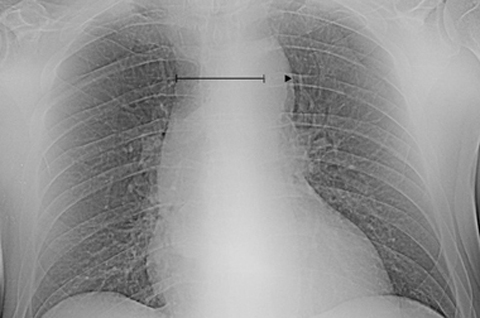

Besides elevation of the d-dimer level, the clinical suspicion for aortic dissection should also be heightened if the chest radiograph is abnormal (Box 1). Mediastinal widening (relative mediastinum to chest-width ratio > 0.25;11 Figure A) is the most common radiographic finding in aortic dissection.7 Of note, absolute estimations of the mediastinal width are practically inaccurate, as these measurements are influenced by the distance between the roentgenographic source and the thorax.12 It is worth mentioning that one in three patients with aortic dissection has a normal chest x-ray.11 Thus, relying on chest radiography alone as the initial diagnostic modality is inefficient as it clearly carries a high risk of misdiagnosis.